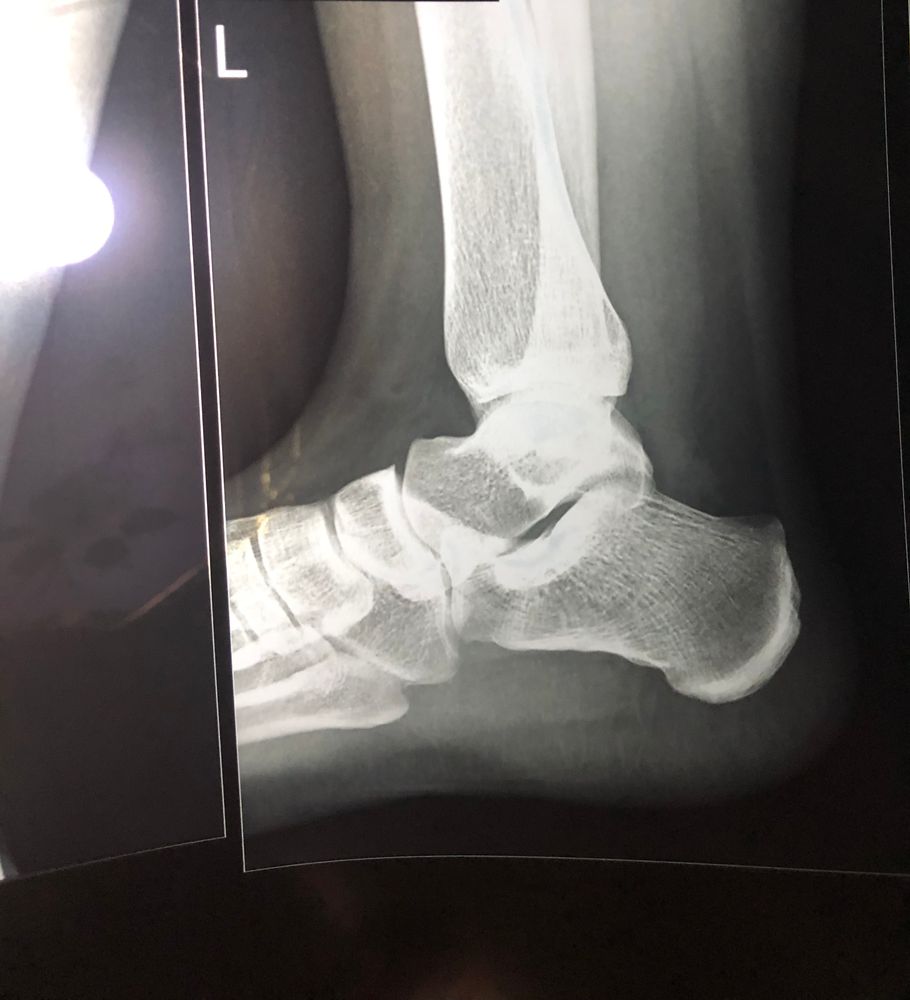

Рентген голеностопа

Елена, ну о чем вы, нога болит с мая, вот наконец зачесался клиент, какая травматология - это экстренный раздел. Могу даже предсказать, аркоксию назначат, можно пить в ожидании приема. Ну и да, как терапевт так и хирург назначат рентген, причем обе проекции, а не как тут. А также НПВС.

Жанна, у меня снимок в двух проекциях, сюда только один скинула, на другом тоже ничего особенного. И не было у меня времени и возможности идти в больницу. Я живу далеко, очень много дел, только сейчас появилось время. Точно так же в августе 2020 упала. В январе 2021 нога начала тревожить сильной болью. В конце марта 2021 только операцию сделали на коленку. Ежу понятно, что нужно своевременно обращаться, но когда дел вагон, и медицина такая, что ближайший талон к терапевту в декабре, где один фиг остаётся терпеть. Пока к терапевту попадёшь, через 2-3 недели к ортопеду, там пока назначат то-се, пока сдашь и попадёшь опять на приём - ещё месяц пройдёт. А у меня тупо нет времени на это - это удел бабулек, у которых времени вагон ходить за 100500 талонами и направлениями . Я получила травму и не думала, что будет болеть так долго и так сильно, потому что думала, что это просто ушиб, который и без того знала чем помазать. Кто же знал, что все полгода будет такая ерундистика Да и жизнь такая, что в первую очередь дела, потом здоровье.